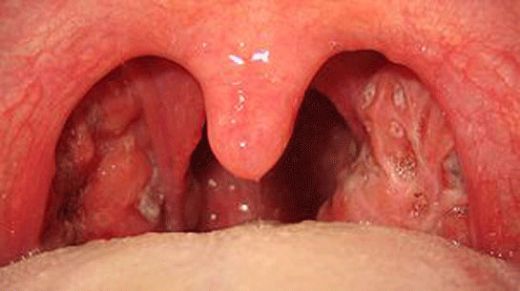

Bademcik ameliyatı, tıpta tonsillektomi olarak bilinen bir prosedürdür. Bu ameliyat, bademciklerin iltihaplanması, enfeksiyon, veya diğer sağlık sorunları nedeniyle gerekli görüldüğünde uygulanır. Ancak, her cerrahi işlemde olduğu gibi, bademcik ameliyatının da belirli riskleri ve sonrası için dikkat edilmesi gereken faktörler bulunmaktadır. Bademcik Ameliyatının Nedenleri Bademcik ameliyatı genellikle aşağıdaki nedenlerden dolayı yapılır:

Ameliyatın Riskleri Bademcik ameliyatı sırasında ve sonrasında çeşitli risklerle karşılaşılabilir. Bu riskler arasında şunlar bulunmaktadır: